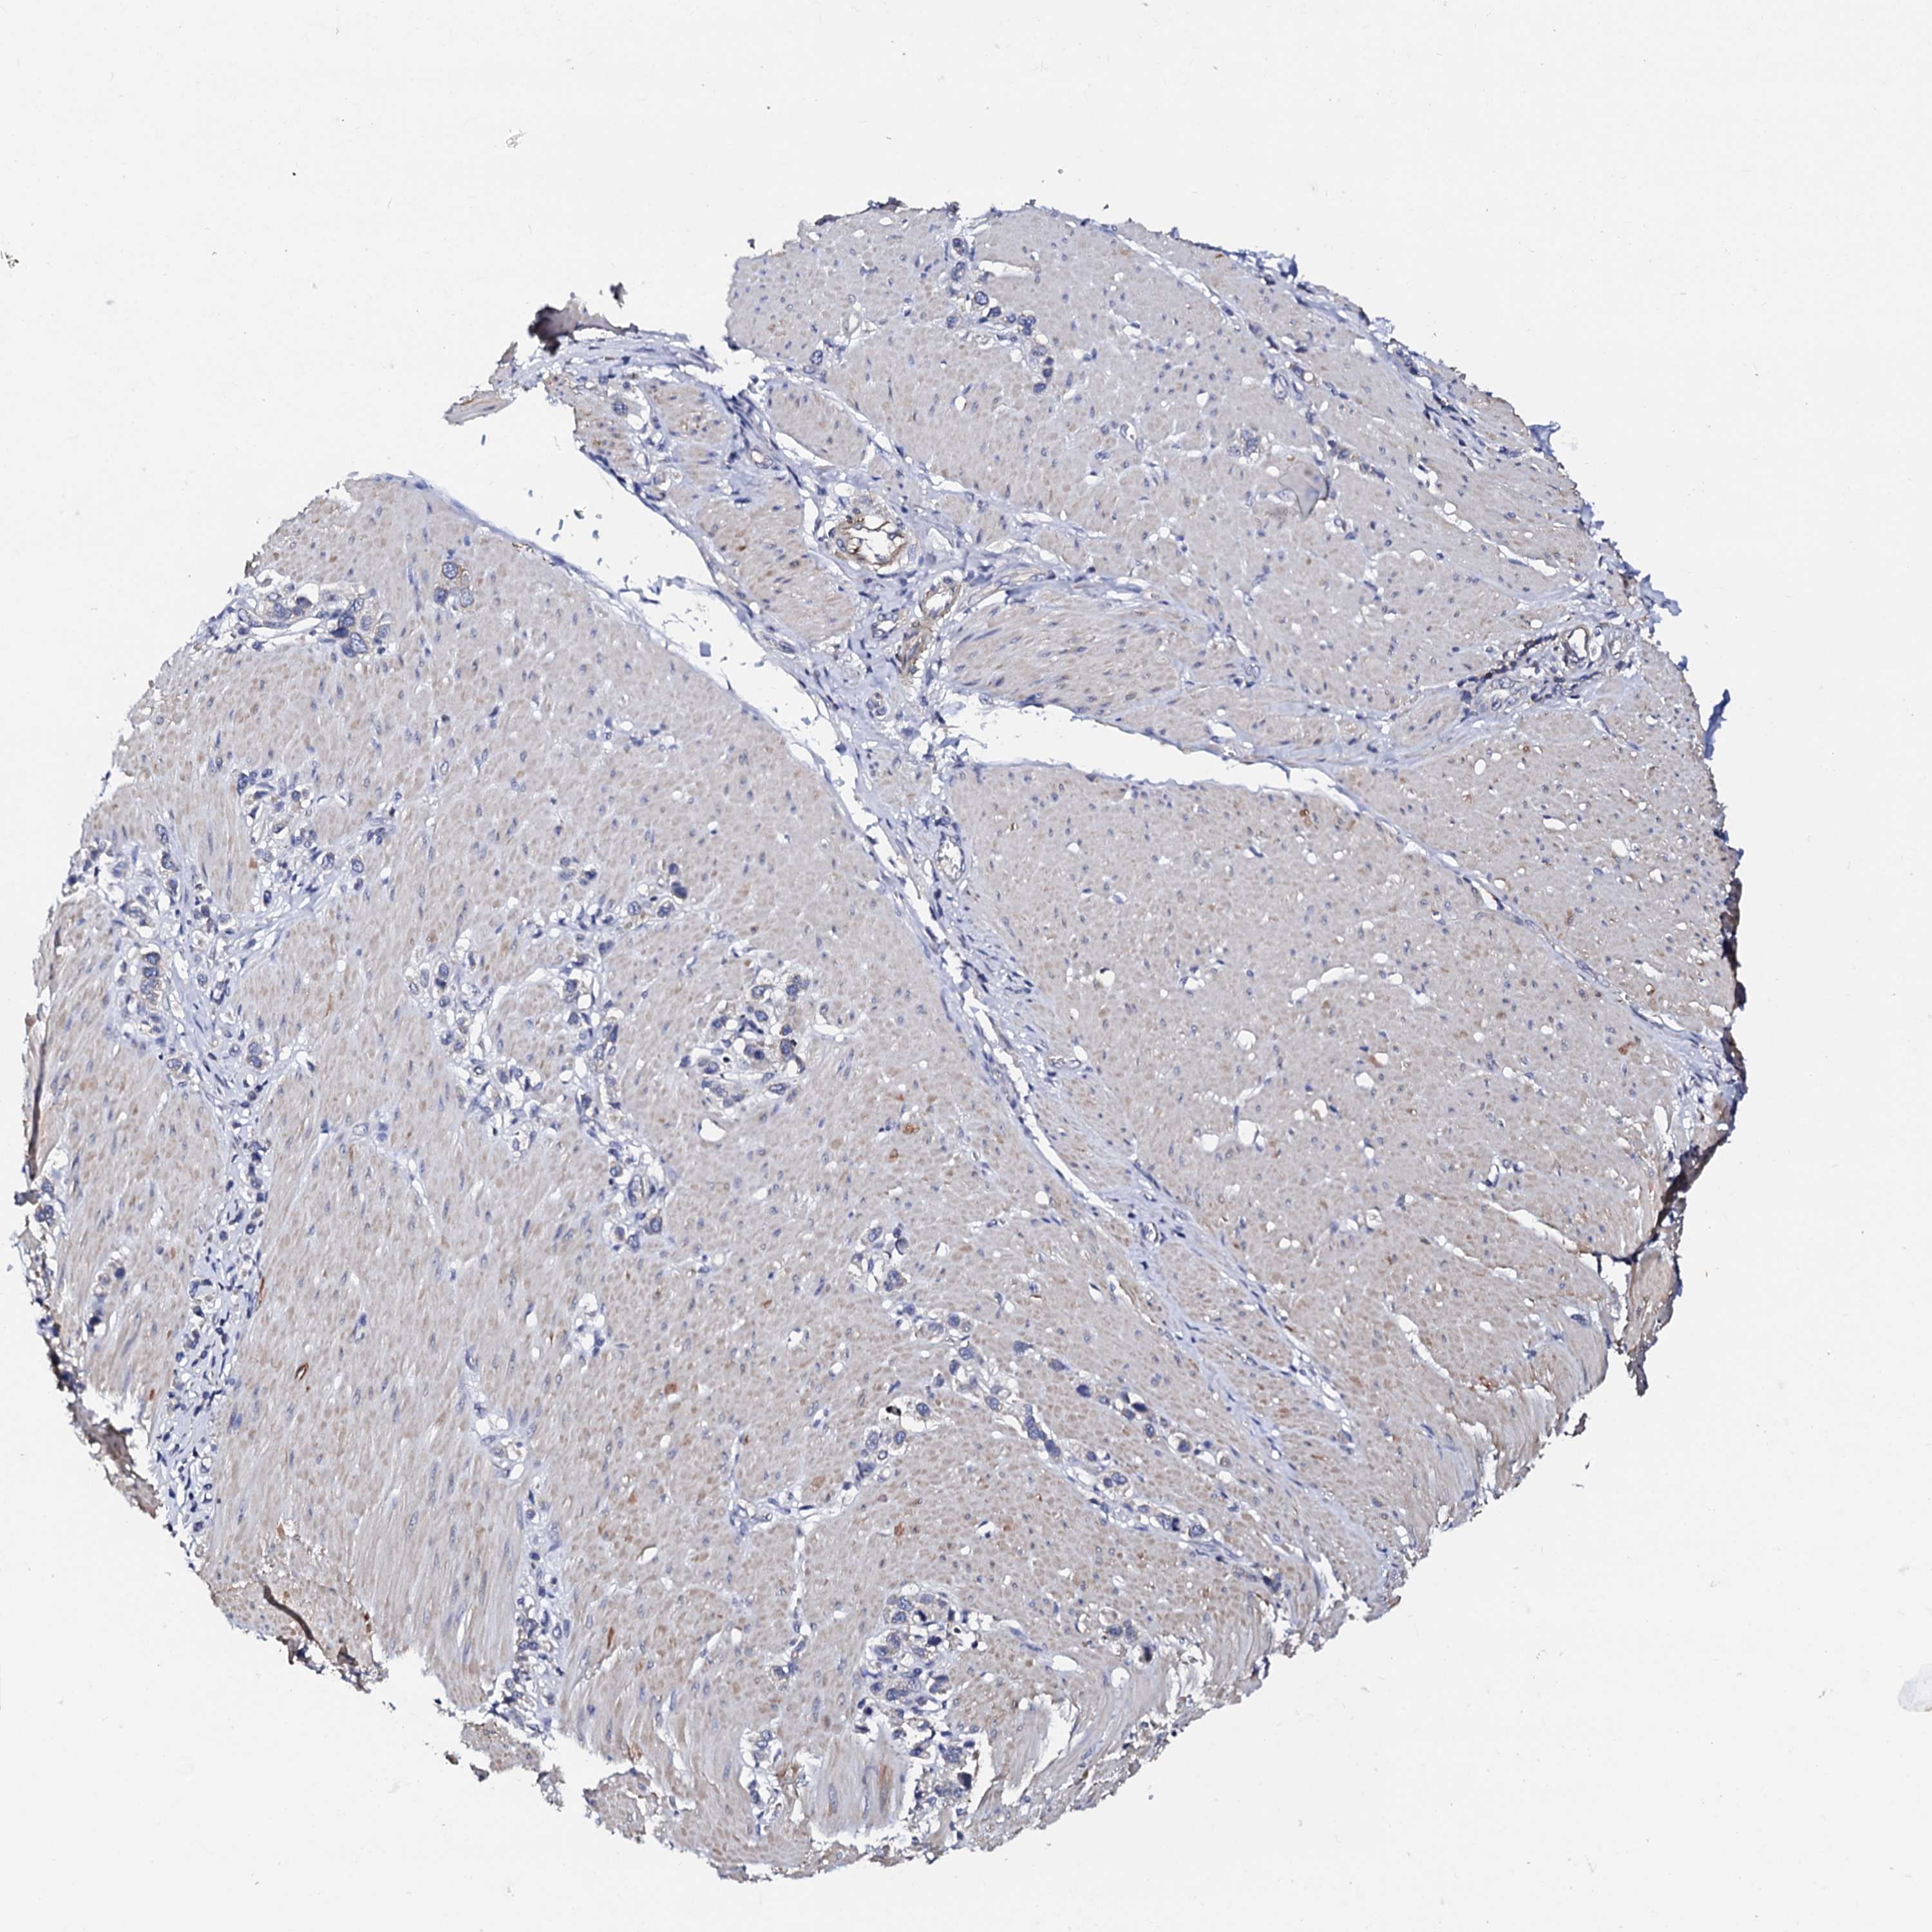

STOMACH CANCER - Protein expressioni

A mouse-over function shows sample information and annotation data. Click on an image to view it in a full screen mode. Samples can be filtered based on level of antibody staining by selecting one or several of the following categories: high, medium, low and not detected. The assay and annotation is described here.

Note that samples used for immunohistochemistry by the Human Protein Atlas do not correspond to samples in the TCGA dataset.

Antibody stainingi

Antibody staining in the annotated cell types in the current human tissue is reported as not detected, low, medium, or high, based on conventional immunohistochemistry profiling in selected tissues. This score is based on the combination of the staining intensity and fraction of stained cells.

Each image is clickable and will lead to virtual microscopy that enables deeper exploration of all samples and also displays staining intensity scores, fraction scores and subcellular localization as well as patient and tissue information for each sample.

Antibody HPA039360

Staining

High

Medium

Low

Not detected

Intensity

Strong

Moderate

Weak

Negative

Quantity

>75%

75%-25%

<25%

None

Location

Nuclear

Cytoplasmic/membranous

Cytoplasmic/membranous,nuclear

Adenocarcinoma, NOS